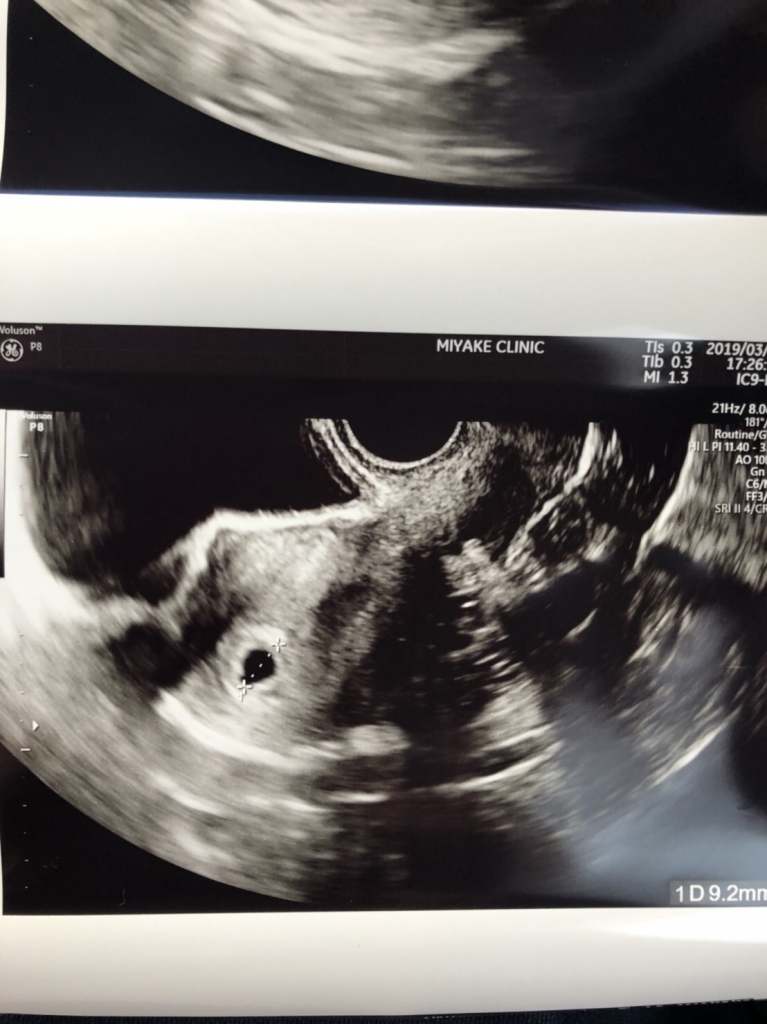

こんにちは! 命のリレー・ナビゲーター、服部雄志です 昨日お客さまからご報告がありました 内容は、「赤ちゃんの袋が見えました!」ということで 胎嚢確認の嬉しいご連絡です 許可をいただいたのでエコー画像をご紹介しますね 可愛いですね かわいいですけど、確かな命です そして今回のご懐妊にはもう一つの意味があります それは… 昨年10月20日の子宝セミナーにご参加されて ...

福々ふくべ | 2019.03.28 Thu 16:44